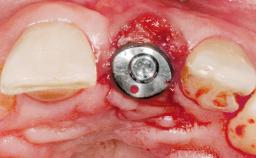

Type of Implants One-Piece

Placement Protocol Immediate implant placement

Loading Protocol Immediate

Retention Screw-retained Screw-retained